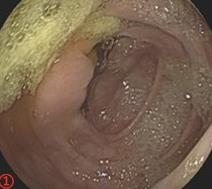

摘要:目的 探讨利那洛肽联合西甲硅油与复方聚乙二醇电解质散(PEG)对便秘患者肠道清洁效果的有效性和安全性。方法 采用前瞻性随机对照试验,通过单盲法,纳入2023年4月-2024年8月于该院消化内镜中心行结肠镜检查的便秘患者383例,随机分为常规组(128例)、实验A组(128例)和实验B组(127例)。常规组采用3 L PEG(Ⅰ)溶液,实验A组采用290 μg利那洛肽 + 2 L PEG溶液,实验B组采用290 μg利那洛肽 + 30 mL西甲硅油+2 L PEG溶液。比较3组患者的肠道准备效果[Boston肠道准备量表(BBPS)评分和去泡效果]、病变检出率、首次排便间隔时间、排便次数、盲肠插管成功率、进镜时间、退镜时间、不良反应发生率和重复检查意愿等。结果 3组患者BBPS评分比较,差异无统计学意义(P > 0.05);实验B组的去泡效果评分明显低于常规组和实验A组,差异均有统计学意义(P < 0.05);实验B组的病变总检出率和息肉检出率明显高于常规组和实验A组,差异均有统计学意义(P < 0.05);常规组的首次排便间隔时间明显长于实验A组和实验B组,差异均有统计学意义(P < 0.05);3组患者排便次数比较,差异无统计学意义(P > 0.05);3组患者盲肠插管成功率均为100.0%,进镜时间相当,差异均无统计学意义(P > 0.05);实验B组的退镜时间明显短于常规组和实验A组,差异均有统计学意义(P < 0.05);常规组腹胀腹痛发生率和不良反应总发生率明显高于实验A组和实验B组,差异均有统计学意义(P < 0.05);常规组重复检查意愿率明显低于实验A组和实验B组,差异均有统计学意义(P < 0.05)。结论 290 μg利那洛肽联合30 mL西甲硅油与2 L PEG溶液方案在便秘患者肠道准备上具有优势,较3 L PEG溶液和290 μg利那洛肽+2 L PEG溶液方案,可获得更好的肠道清洁效果,且安全性和患者重复检查意愿率高,可作为便秘患者肠道准备的推荐方案。